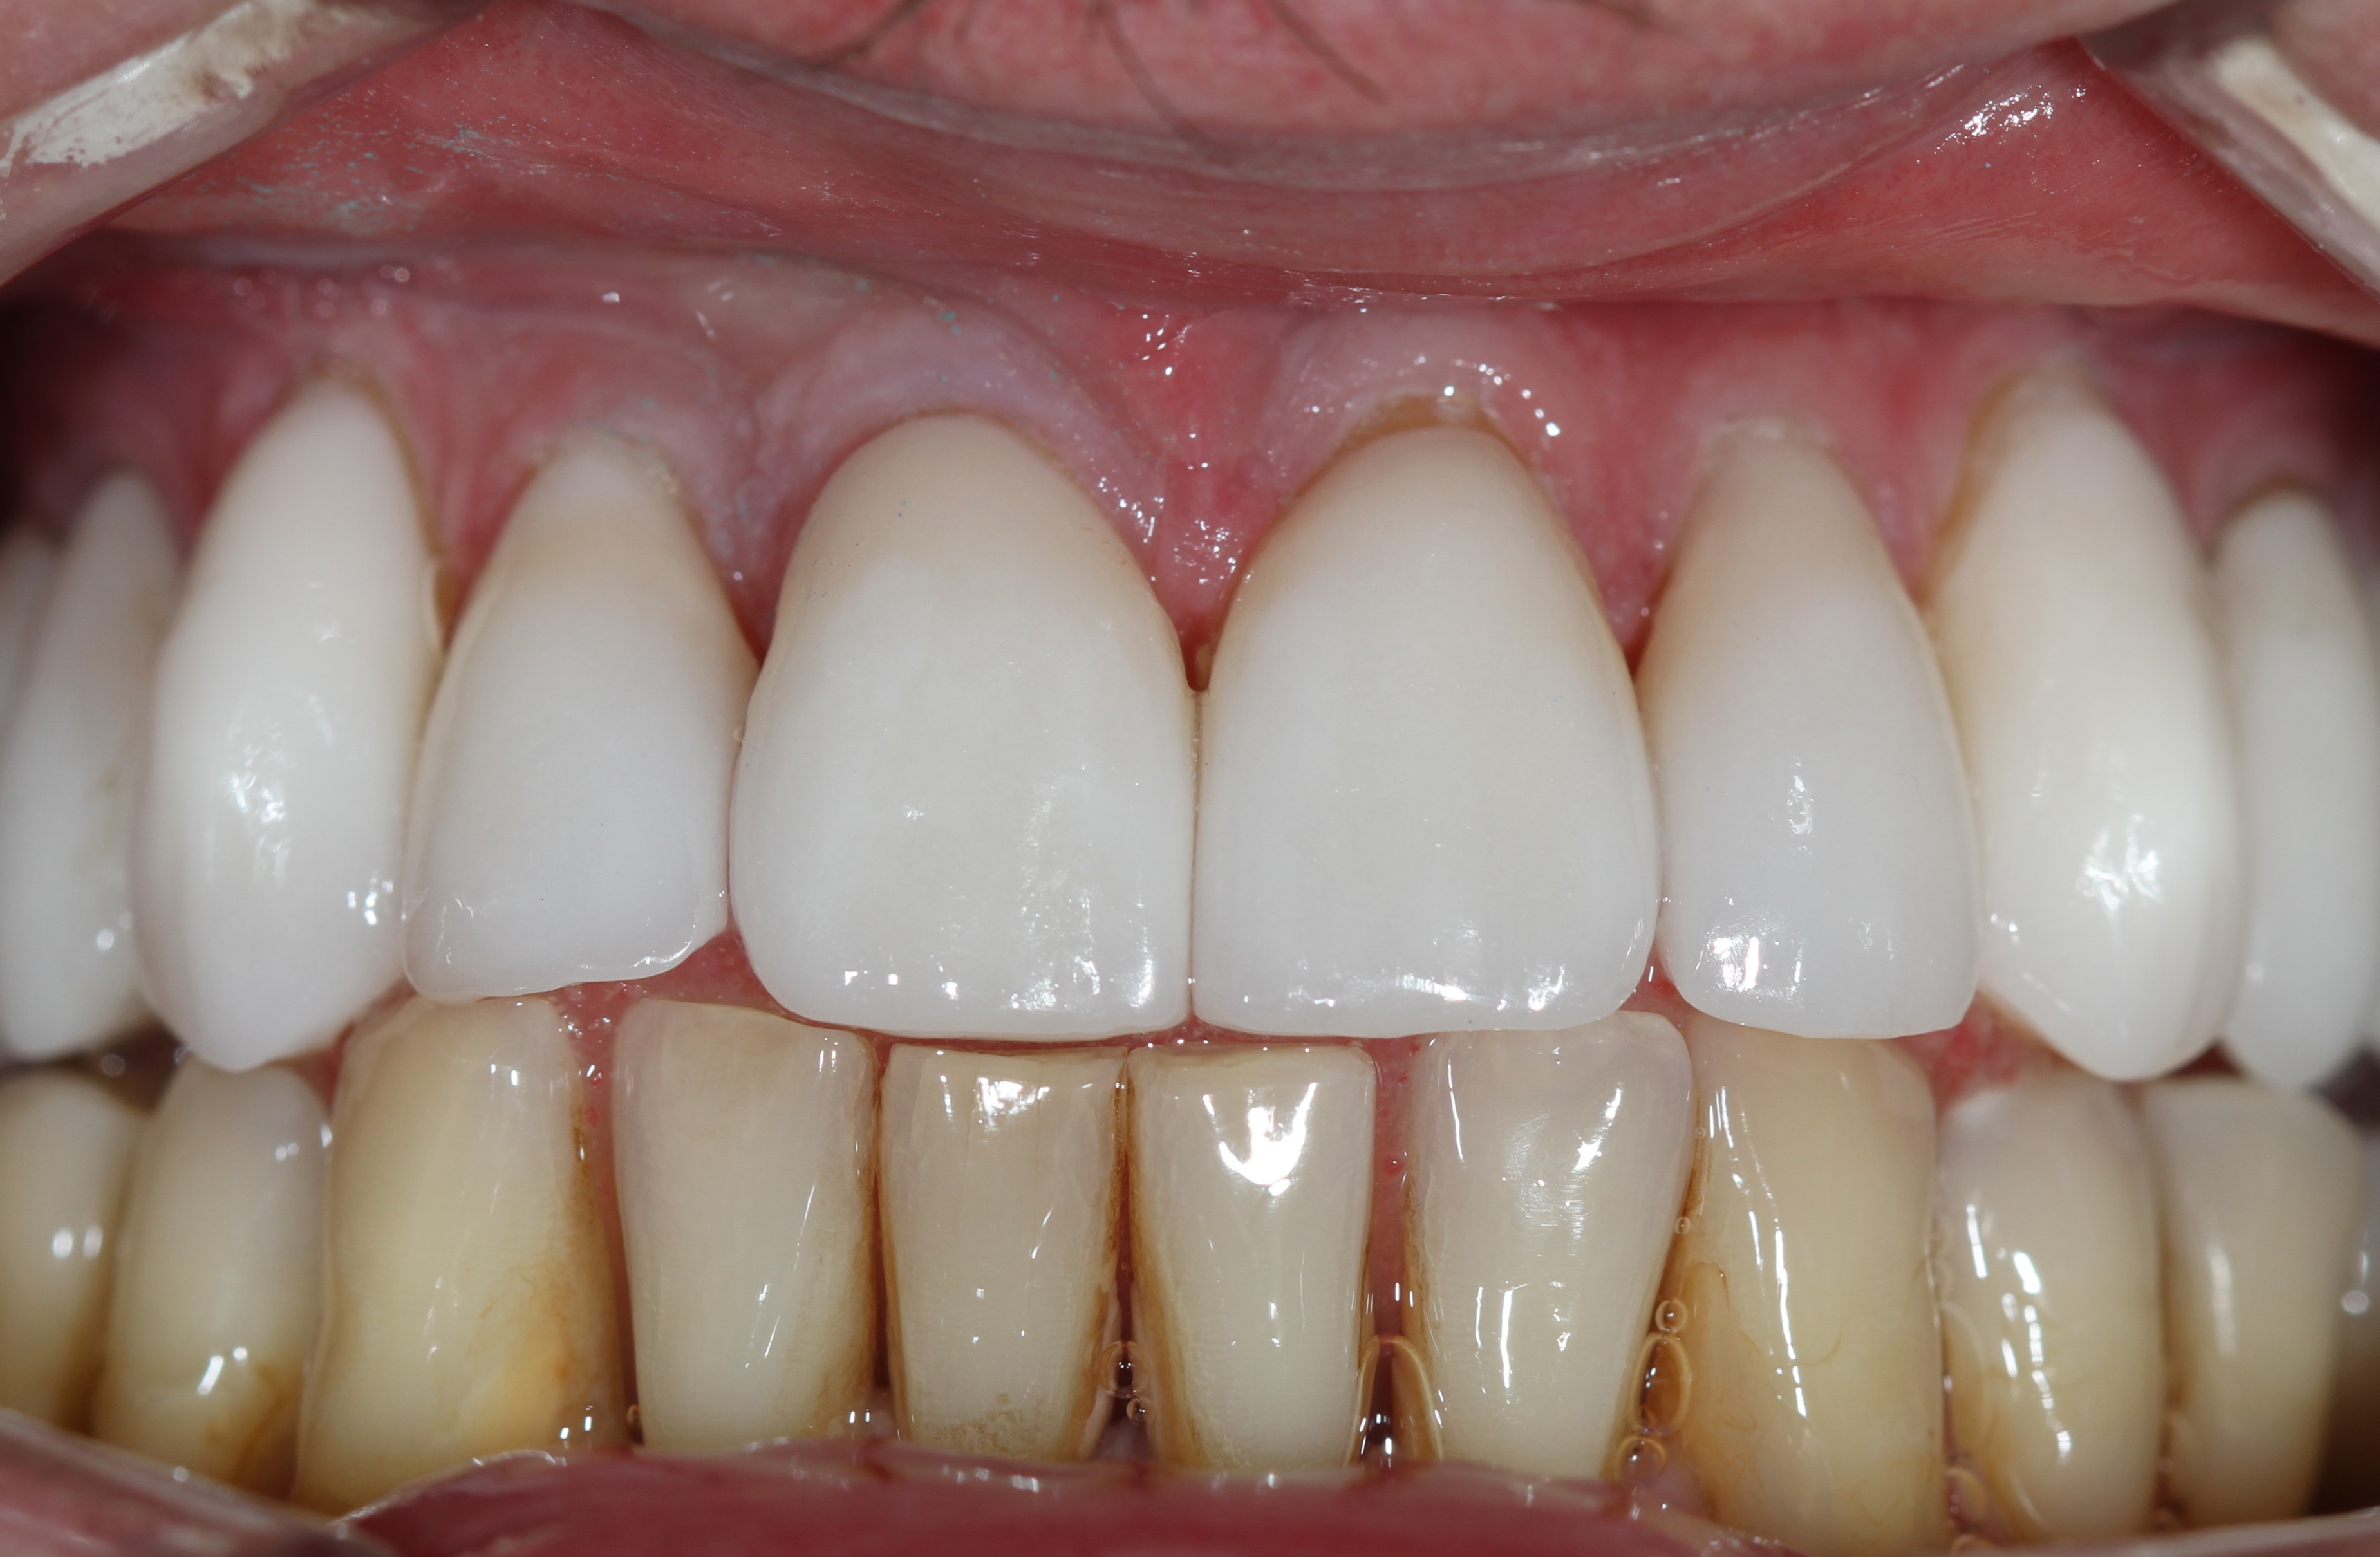

Это виниры на рефракторе . 12 зуб коронка на оксиде циркония.

Снова виниры

Замена старых виниров темного цвета на более светлые по причине оголения шейки зуба.

Виниры цвета BLEACH

Установлены керамические виниры на верхнюю челюсть по эстетическим требованиям.